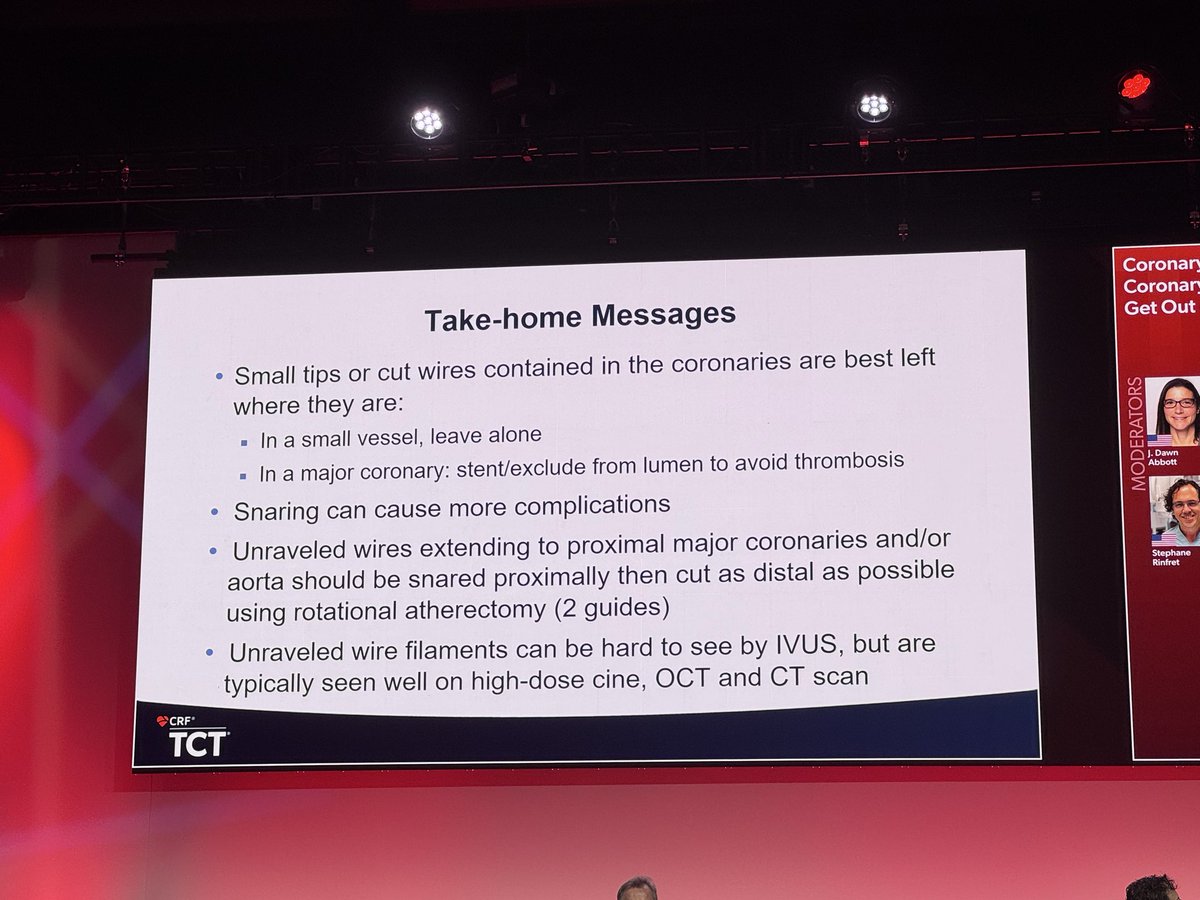

Lost MC tips and unraveled wire, cut with rota!!! #CardioX #CardioTwitter #CardioEd #CardioResearch @BurkhoffMd @djc795 @ColletCarlos @georgedangas @jgranadacrf @MartyBLeon @Drroxmehran @sahilparikhmd @PopmaJeffrey @triciarawh @mirvatalasnag @TCTConference @TCTMD @jedicath…

Lost MC tips and unraveled wire, cut with rota!!! #CardioX #CardioTwitter #CardioEd #CardioResearch @BurkhoffMd @djc795 @ColletCarlos @georgedangas @jgranadacrf @MartyBLeon @Drroxmehran @sahilparikhmd @PopmaJeffrey @triciarawh @mirvatalasnag @TCTConference @TCTMD @jedicath…